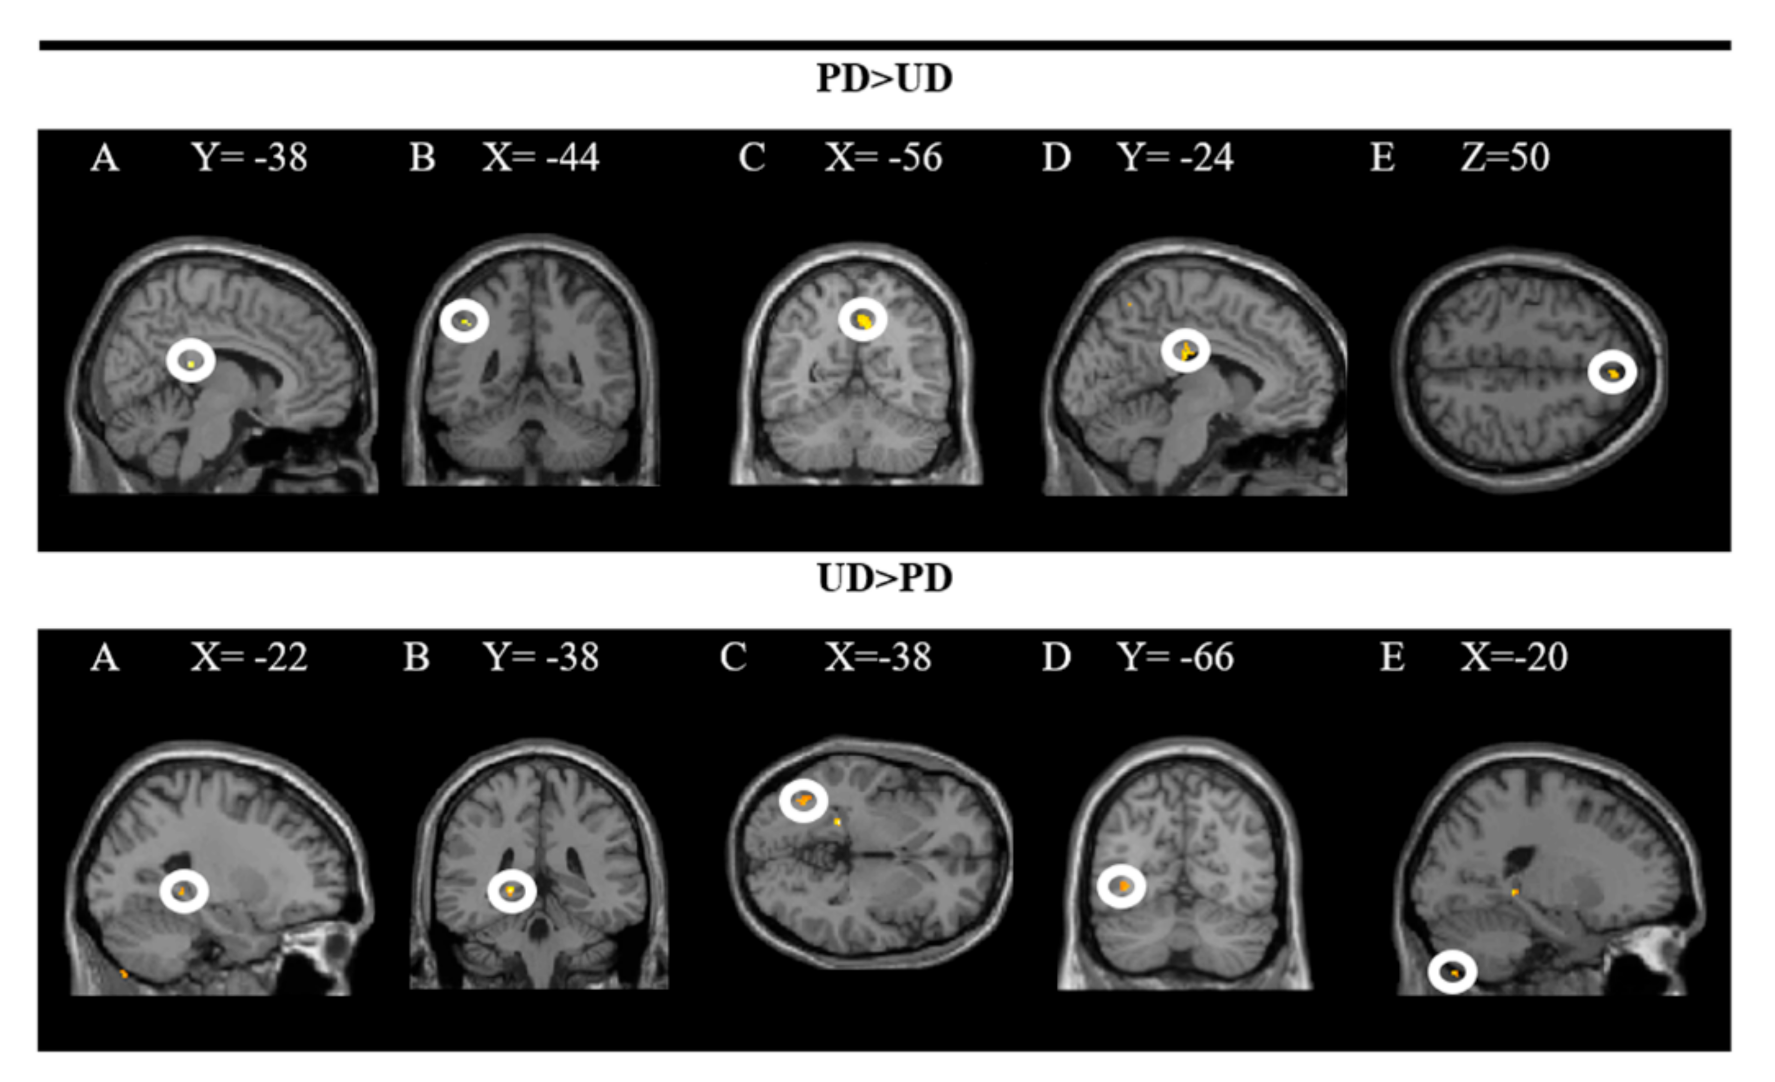

The groups in the rear R cingulate gyrus, L inferior parietal lobe, R pre(cuneus), L middle cingulate gyrus, and R superior frontal gyrus were activated more strongly when comparing the pleasant (PD × RD + PD × ED) and the unpleasant (UD × RD + UD × ED) plates. In contrast, the L hippocampus, L inferior occipital gyrus, and L exterior of the cerebellum were activated more significantly when comparing unpleasant to pleasant dishes. In these analyses, a significance level of p = 0.001 was established without correction. The results are presented in Figure 3 and the coordinates of the peak are in Table 1.

Figure 3.

Brain regions activated more strongly to pleasant vs. unpleasant dishes (PD > UD) and to unpleasant vs. pleasant dishes (UD > PD).

The upper part of the figure shows a T-map with a threshold of p < 0.0001 uncorrected for multiple comparisons (T > 3.2), which is superimposed on the mean anatomical image of all subjects (NIM-space). A: R posterior cingulate gyrus; B: L inferior parietal lobe; C: R precuneus; D: L middle cingulate gyrus; E: R superior frontal gyrus. The lower part shows an uncorrected threshold T map at p < 0.0001 for multiple comparisons (T > 4.5), which is superimposed on the mean anatomical image of all subjects (MNI-space). A and B: L hippocampus; C and D: L inferior occipital gyrus; E: L outer cerebellum. See the corresponding coordinates of the peaks in Table 1.